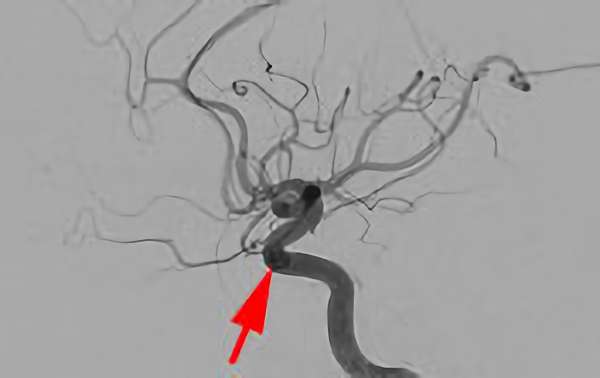

No.1631 手術中